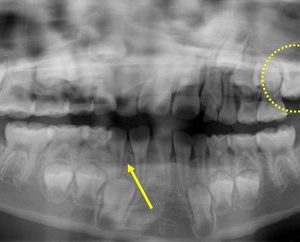

続きを読む7歳の女の子、下あごの前歯が1本少ないと相談に来られました。レントゲン撮影したところ下あごの前歯(黄色矢印)が1本先天的にないことがわかりました(左上6歳臼歯の萌出が遅れています)。現在、下あごの前歯の部分は3本の永久 ...